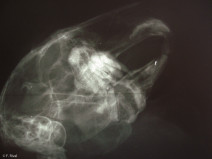

• Journée d'imagerie en ophtalmologie

Pour sa deuxième édition, la journée d’imagerie en ophtalmologie vous propose cette année de vous familiariser avec les nouvelles technologies disponibles en médecine vétérinaire. Les bases étant à présent acquises, les présentations ont pour objectif d’apporter aux participants une réelle plus-value dans leur pratique quotidienne. Les orateurs, spécialistes en ophtalmologie, en imagerie ou rec...